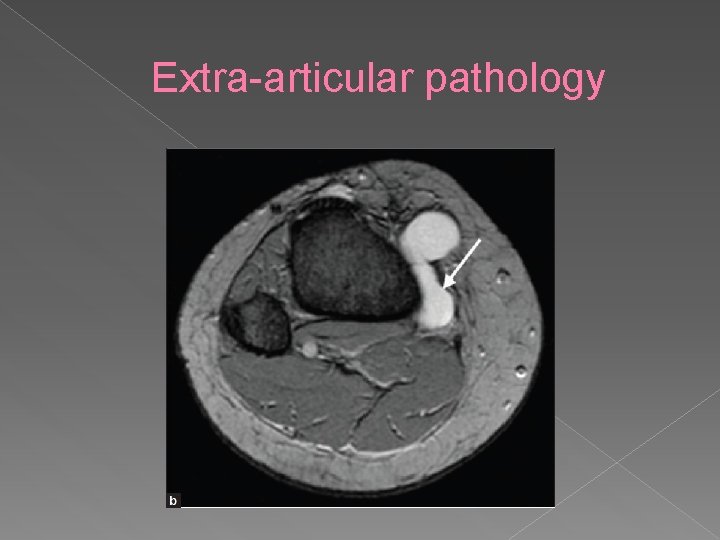

Extra-articular pathology